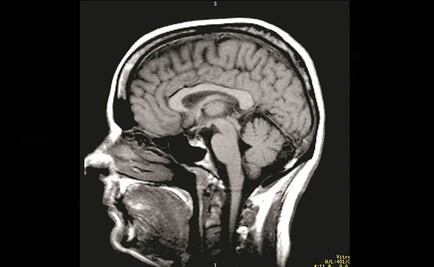

La secreción es capaz de permear la densa protección cerebral que cuarta los efectos de un medicamento

El receptor GPR3 puede ayudar a eliminar una placa tóxica que se acumula en el cerebro de los enfermos